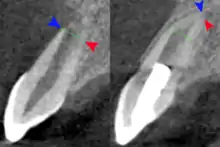

Regenerative endodontics in 10-year-old with necrotic pulp and incomplete root formation (left) then 1 year after treatment. Buccal aspect of apex (blue arrow), palatal aspect of apex (red arrow) and line of initial root formation (green line)